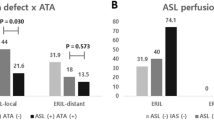

The proportions of stable radiomic features in the first group were 13.8% (82/595) in EPI-T2-FLAIR and 5.5% (33/595) in ETL-T2-FLAIR for acute ischemic hyperintensity and 15.6% (93/595) in EPI-T2-FLAIR and 5.1% (30/595) in ETL-T2-FLAIR for chronic ischemic hyperintensity. Proportions of stable radiomic features in the second group were 16.8% (100/595) in TR-T2-FLAIR and 1.8% (11/595) in ETL-T2-FLAIR for acute ischemic hyperintensity and 13.0% (77/595) in TR-T2-FLAIR and 0.7% (4/595) in ETL-T2-FLAIR for chronic ischemic hyperintensity. EPI-T2-FLAIR and TR-T2-FLAIR showed significantly higher proportions of stable radiomic features than those of ETL-T2-FLAIR (p < 0.001). Proportions of stable radiomic features in the first group were 9.7% (58/595) in the EPI-T2-FLAIR intersection and 3.4% (20/595) in the ETL-T2-FLAIR intersection for acute ischemic hyperintensity and 18.0% (107/595) in the EPI-T2-FLAIR intersection and 11.6% (69/595) in the ETL-T2-FLAIR intersection for chronic ischemic hyperintensity. Proportions of stable radiomic features in the second group were 12.1% (72/595) in the TR-T2-FLAIR intersection and 3.9% (23/595) in the ETL-T2-FLAIR intersection for acute ischemic hyperintensity and 9.6% (57/595) in the TR-T2-FLAIR intersection and 1.2% (7/595) in the ETL-T2-FLAIR intersection for chronic ischemic hyperintensity. EPI-T2-FLAIR and TR-T2-FLAIR showed significantly higher proportions of stable radiomic features than those of ETL-T2-FLAIR (p < 0.002). The detailed results are listed in Table 1.

Heat maps of radiomics features extracted from whole- and intersection ROI masks in the first and second groups. Features with CCC > 0.85 were regarded as stable. (a) Features from whole ROI masks in the first group. (b) Features from whole ROI masks in the second group. (c) Features from intersection ROI masks in the first group. (d) Features from intersection ROI masks in the second group. AIH acute ischemic hyperintensity, CIH chronic ischemic hyperintensity, CCC concordance correlation coefficients, ROI region-of-interest, EPI echo-planar imaging, ETL echo train length, TR repetition time.

Proportions of stable radiomic features extracted from whole- and intersection ROI masks on each fast scanned T2-FLAIR sequence in the first and second groups. (a,b) Proportions of stable radiomic features from whole ROI masks (a) and intersection ROI masks (b) according to each fast scanned T2-FLAIR. (c,d) Numbers of stable radiomic features from whole ROI masks (c) and intersection ROI masks (d) according to each fast scanned T2-FLAIR. AIH acute ischemic hyperintensity, CIH chronic ischemic hyperintensity, ROI region-of-interest, EPI echo-planar imaging, ETL echo train length, TR repetition time, GLCM gray-level co-occurrence matrix, GLRLM gray-level run-length matrix, LBP local binary pattern, GLSZM gray-level size zone matric, NGTDM neighboring gray tone difference matrix.

Proportions of stable radiomic features throughout both fast scanned T2-FLAIR sequences extracted from whole- and intersection ROI masks in the first and second groups. (a,b) Proportions of stable radiomic features from whole ROI masks (a) and intersection ROI masks (b). (c,d) Numbers of stable radiomic features from whole ROI masks (c) and intersection ROI masks (d). AIH acute ischemic hyperintensity, CIH chronic ischemic hyperintensity, ROI region-of-interest, EPI echo-planar imaging, ETL echo train length, TR repetition time, GLCM gray-level co-occurrence matrix, GLRLM gray-level run-length matrix, LBP local binary pattern, GLSZM gray-level size zone matric, NGTDM neighboring gray tone difference matrix.